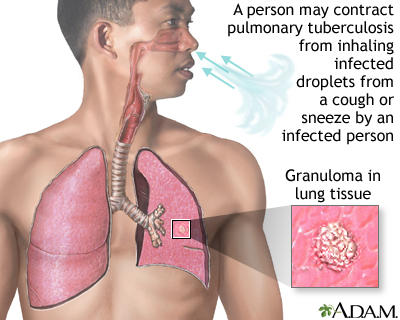

Pulmonary TB is caused by the bacterium Mycobacterium tuberculosis (M tuberculosis). TB is contagious. This means the bacteria may spread from an infected person to someone else. You can get TB by breathing in air droplets from a cough or sneeze of an infected person. The resulting lung infection is called primary TB.